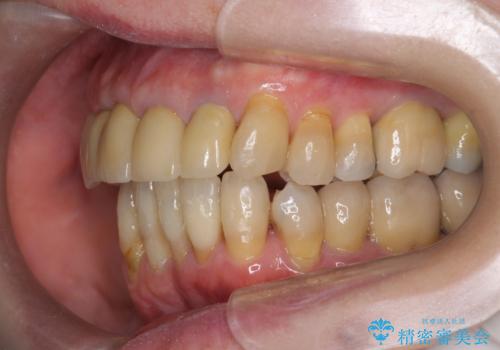

矯正治療が終わったのちに、精度の高いセラミックを装着することでより安定した噛み合わせとなり審美性も兼ね備えた口腔内状態で治療を終了し、今後のメンテナンスを行っていくことができます。